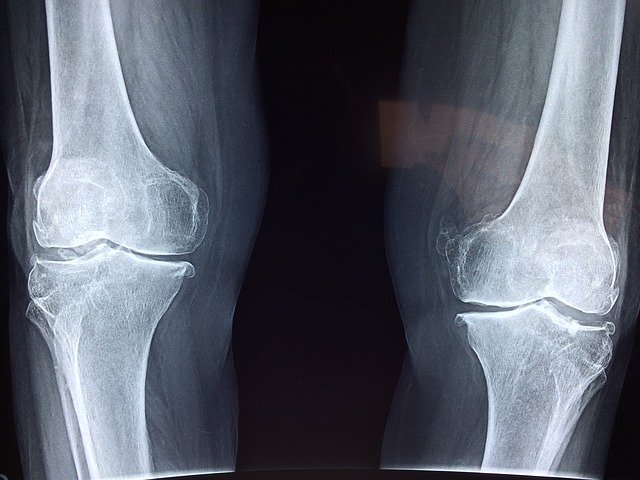

3. 관절 경직

류마티스 관절염 초기 증상 세 번째는 관절 경직입니다. 관절이 점차 뻣뻣해지고 굳은 느낌이 드는 경우에는 류마티스 관절염을 의심해볼 수 있습니다. 특히 자고 일어나거나 겨울 등 환경에 따라서 관절이 잘 안 움직여지며 이러한 증상이 30분 이상 지속되는 경우 병원에 방문해 진료받는 것이 바람직합니다.